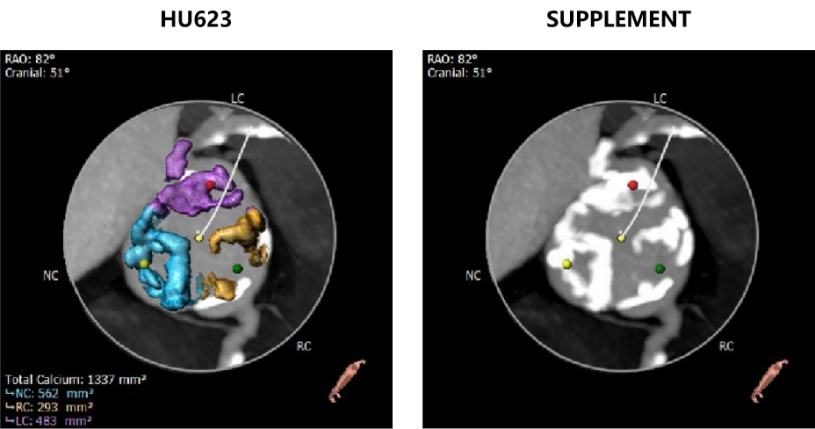

主动脉瓣瓣环周长70.8mm,平均周长径 22.6mm,SOV:31.9mm*28.0mm*29.0mm,瓣叶增厚,瓣上见明显钙化,瓣环水平夹角48°,左冠高度12.2mm,右冠高度15.5mm,HU850钙化积分704mm³。

HU623钙化积分1337mm³,主动脉弓见大量钙化。